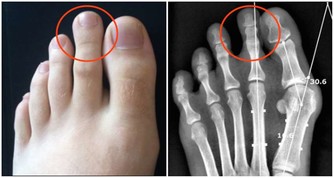

8. 搓足

先用左手搓右足底20下,再用右手搓左足底20下。足部是人的“第二心臟”,可以促進血液的循環,激化和增強內分泌系統機能,加強人體的免疫和抗病的能力,並可增加足部的抗寒性。